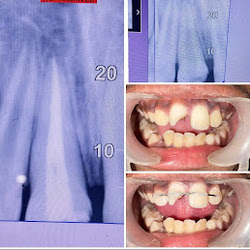

Welcome to our gallery

See how our company transforms ideas into reality. This gallery is a visual testament to our work and achievements.